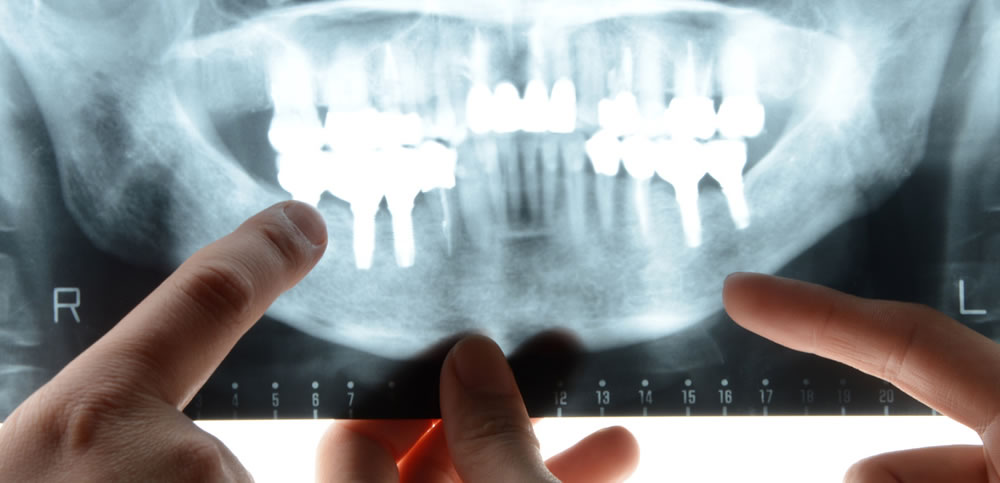

インプラント治療は一般の歯科治療とは異なり口腔外科となるため、より安全に行える準備や環境が重要となり、オペの際には、顎骨周辺の血管や神経を損傷するリスク等も少なからずあるため、的確に処置が行える優秀な歯科医師の存在も重要となってきます。

当院では、リスクを最小限に抑えたインプラント治療をご提供するため、CTによる精密診断をはじめ、様々な医療器具を整えています。確かな技術と精密機器の融合で、患者様に適切なインプラント治療を実施致します。

サージカルガイドで正確な埋入

歯科用CTのデータを基に、ガイドを作製して事前のシミュレーションを実施しております。作製されたガイドを使用して埋入手術を行なう事で、埋入場所、角度、深さなどのズレを防止して、人為的ミスを無くし、正確かつスムーズな処置が可能になります。